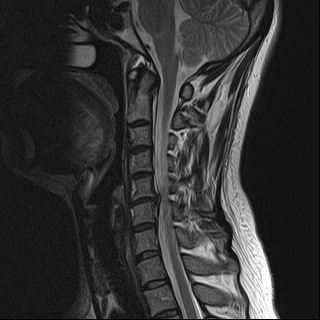

목디스크란?

목을 받쳐주는 뼈를 경추라고 하는데 여기는 뼈가 7개 있고 이 뼈 마디마다 디스크라는것이 있습니다. 이 디스크의 역할은 척추 뼈 사이에 충격을 완화하고 운동할 수 있게합니다. 목디스크는 퇴행성 척추 질환으로 목 주위 근육, 인대가 장기간 압력을 받고 퇴행하여, 디스크가 자신의 역할을 하지 못하고 밀려나고 통증과 같은 목디스크 증상을 보이는 질병입니다. 이 디스크의 위치가 어디에 있는지에 따라 목 이외에도, 손이 저리거나 어깨가 아프고 두통과 같은 다른 목 디스크 증상을 일으킬 수 있습니다. 만약 여러분이 디스크를 그대로 방치하면, 몸이 마비되거나 호흡이 곤란한 상황에 처할 수 있기 때문에 여러분의 관심을 필요로 할 것입니다.

척수라는 중추신경이 목뼈를 통과하고 목 아래 감각과 운동신경에 영향을 미치기 때문에 목디스크 증상이 나타날 경우 신속한 대책이 필요합니다. 목디스크 치료는 일반적으로 초기 단계에서 대부분의 환자가 물리 치료 또는 약물을 통해 개선됩니다. 그렇지 않으면 신경 성형술과 차단술이라는 뼈 주사 목 디스크 치료법을 사용합니다.이 치료법은 통증이 나타나는 신경 부위에 약물을 주입하는 것입니다. 치료로 질병을 완전히 치료하는 것이 아니라 염증을 완화하고 통증을 줄이는 것이 중요합니다.